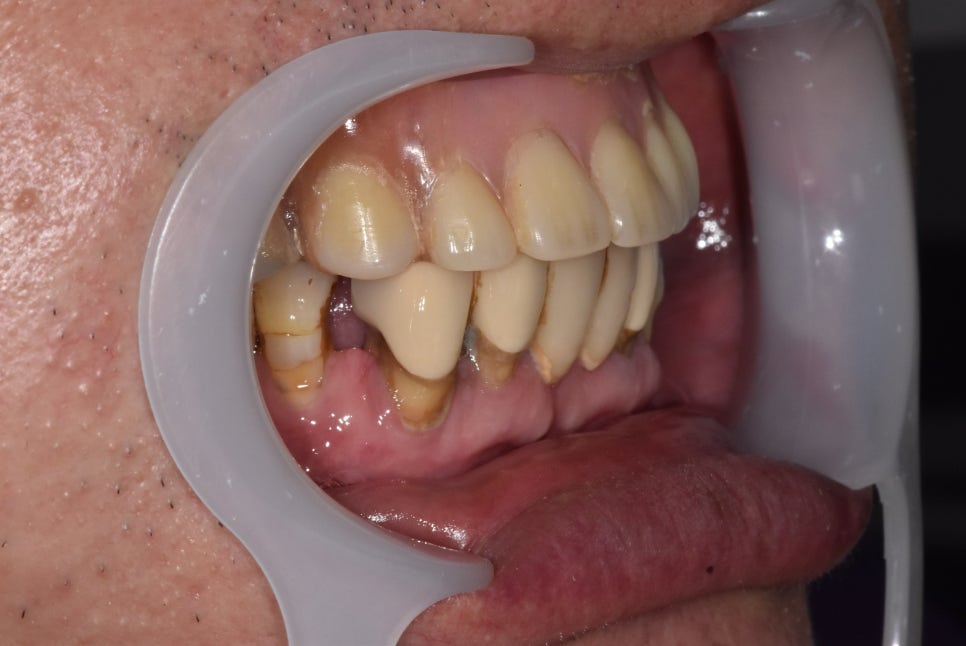

250425

임플란트 머리가 올라간 모습입니다.

잇몸뼈가 처음부터 워낙 얇고 낮아서인지

치아가 좀 길어 보이네요.

꺼진 잇몸을 임플란트로 자연스럽게 보이게끔

제작하기로 했습니다.